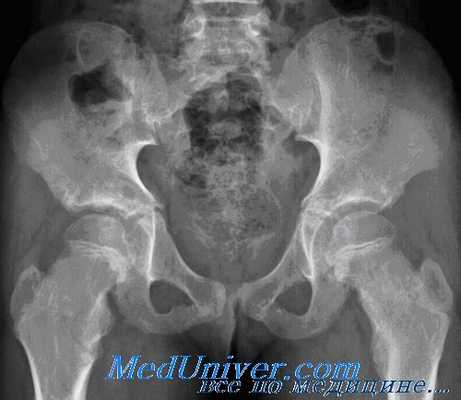

Рентгенограмма при переломе костей таза

- Рентгенография костей таза.

Перелом костей таза – это нарушение целостности одной или нескольких тазовых костей. Местные симптомы включают боль в месте перелома, деформацию таза, видимое укорочение нижней конечности, нарушение движений ногами. Тяжесть травмы связана с большой потерей крови, истекающей из отломков костей таза и мягких тканей, а также развитием травматического шока, обусловленного болевым синдромом и кровопотерей. Диагноз устанавливается по результатам рентгенографии. Для исключения повреждения органов таза могут быть назначены уретрография, цистография, УЗИ мочевого пузыря. Лечение - иммобилизация, иногда с применением скелетного вытяжения. В отдельных случаях показана оперативная фиксация отломков.

Диагностика